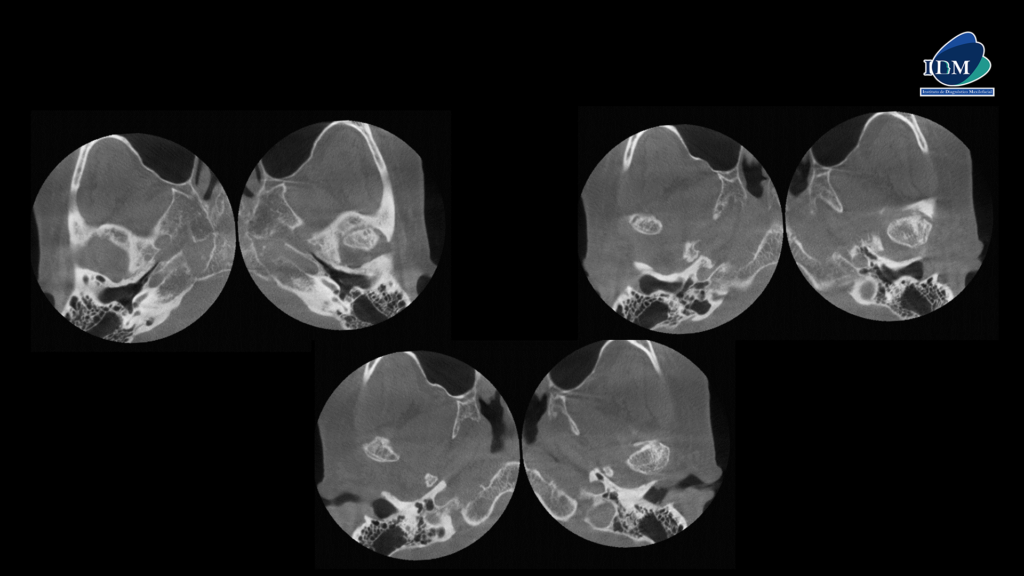

CORTES AXIALES

Así mismo en la tomografía volumétrica de haz cónico a boca abierta se evidencian osteofitos anteriores en ambos cóndilos mandibulares con disminución severa del espacio interarticular, sumado a la alteración de la morfología y estructura condilar. Finalmente, se evidencia una deformación de las vertientes de ambas eminencias articulares.